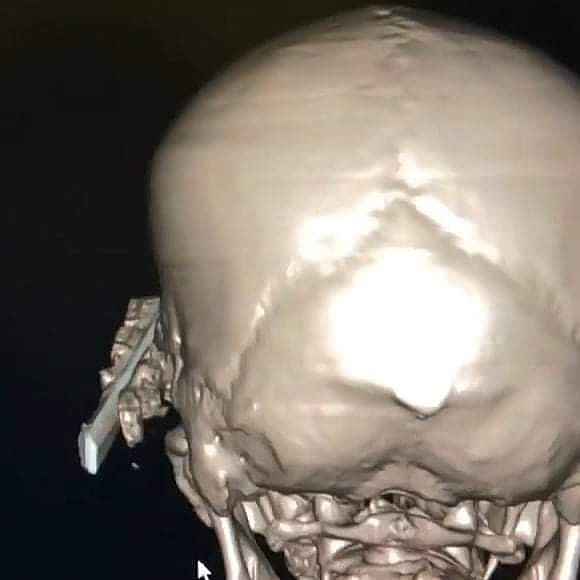

Kastamonu'da uyuduğu sırada koltuktan düşen yaşlı şahsın başına soba maşası saplandı. Maşanın bir kısmı itfaiye ekiplerince kesilirken, kalan kısım ise ameliyatla alındı.

Edinilen bilgiye göre, Araç ilçesinde ikamet eden ve ismi öğrenilemeyen yaşlı şahıs, koltukta uyuduğu sırada düşmesi sonucu kafasına soba maşası saplandı. İhbar üzerine yaralanan yaşlı şahıs, 112 Acil Sağlık ekiplerince Araç Devlet Hastanesine kaldırıldı. Burada ilk müdahalesi yapılan yaşlı şahıs, ardından Kastamonu Devlet Hastanesine sevk edildi. Burada tedavi altına alınan yaşlı şahsın kafasına saplanan soba maşasının bir kısmı, ilk olarak itfaiye ekiplerince kesildi. Ardından kafa tasında kalan kısım ise, yapılan ameliyat ile çıkarıldı. Kafasından soba maşası çıkarılan yaş şahıs, daha sonra servise alınarak tedavisine başlandı.

Edinilen bilgiye göre, Araç ilçesinde ikamet eden ve ismi öğrenilemeyen yaşlı şahıs, koltukta uyuduğu sırada düşmesi sonucu kafasına soba maşası saplandı. İhbar üzerine yaralanan yaşlı şahıs, 112 Acil Sağlık ekiplerince Araç Devlet Hastanesine kaldırıldı. Burada ilk müdahalesi yapılan yaşlı şahıs, ardından Kastamonu Devlet Hastanesine sevk edildi. Burada tedavi altına alınan yaşlı şahsın kafasına saplanan soba maşasının bir kısmı, ilk olarak itfaiye ekiplerince kesildi. Ardından kafa tasında kalan kısım ise, yapılan ameliyat ile çıkarıldı. Kafasından soba maşası çıkarılan yaş şahıs, daha sonra servise alınarak tedavisine başlandı.